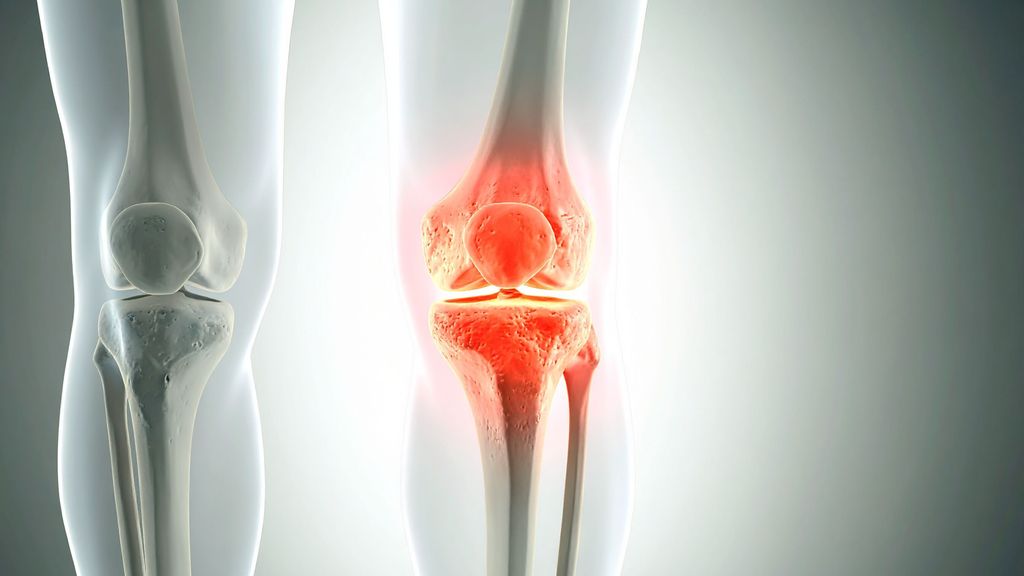

Knorpeldefekte im Knie: AMIC zeigt kurzfristig bessere Ergebnisse als MCI

Knorpeldefekte im Knie können die Lebensqualität einschränken und langfristig zu Arthrose und der Notwendigkeit eines Gelenkersatzes führen. Es gibt diverse Behandlungstechniken, aber ...

Diagnostik und Therapie der Kniegelenkluxation

Luxationen des Kniegelenks sind sehr seltene, aber schwerwiegende Verletzungen, die häufig mit Komplikationen einhergehen und unbehandelt zu schweren Instabilitäten im Knie führen können ...